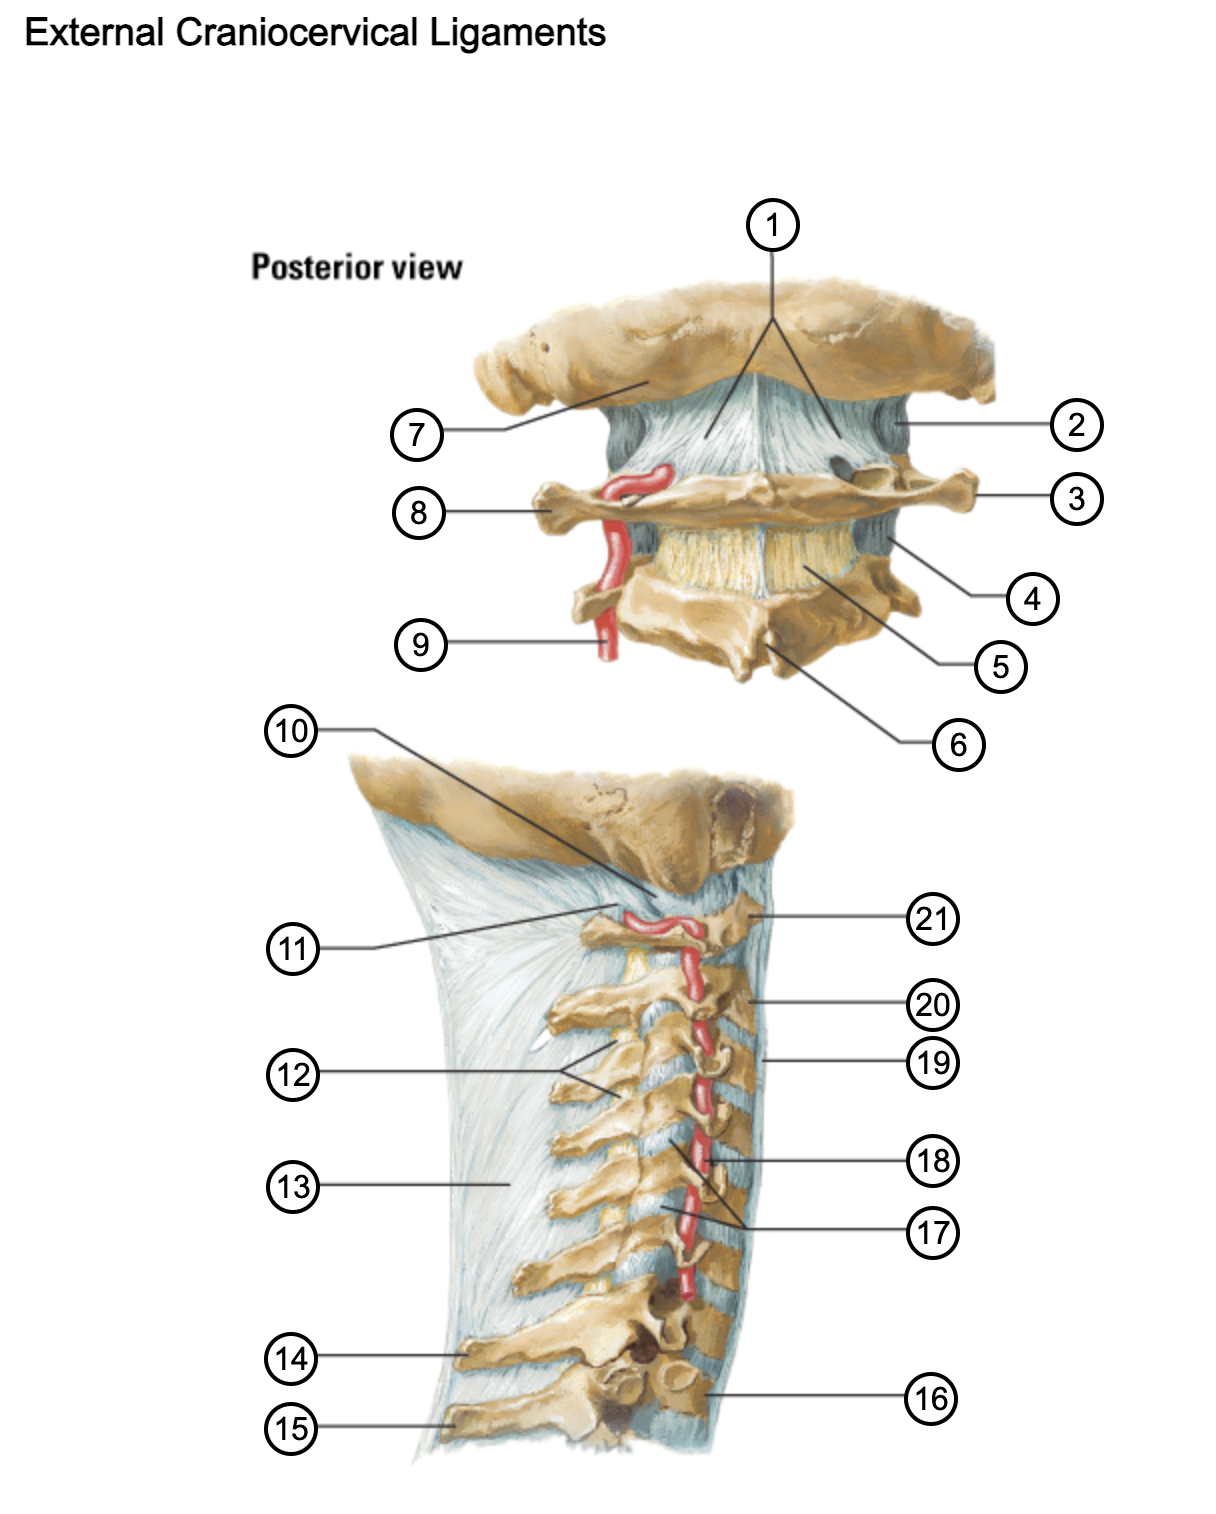

1

posterior antlantooccipital membrane

2

capsule of atlantooccipital joint

3

transverse process of atlas (C1)

4

capsule of lateral atlantoaxial joint

5

ligamenta flava

6

spinous process

7

occipital bone

8

transverse process of atlas (C1)

9

vertebral artery

10

capsule of atlantooccipital membrane

11

posterior atlantooccipital membrane

12

ligamenta flava

13

nuchal ligament

14

spinous process of C7 vertebra

15

spinous process of T1 vertebra

16

T1 vertebra

17

zygapophysical joints (C4-5 and C5-6)

18

vertebral artery

19

anterior longitudinal ligament

20

body of axis

21

Atlas (C1)